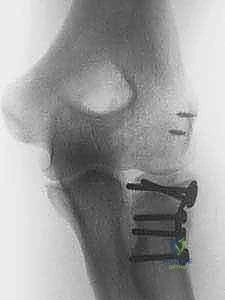

1. التثبيت الداخلي والرد المفتوح (ORIF - Open Reduction and Internal Fixation):

يتم إرجاع قطع العظم المكسورة إلى مكانها التشريحي الدقيق وتثبيتها باستخدام مسامير دقيقة جداً (Micro-screws) وشرائح معدنية صغيرة مصممة خصيصاً لرأس الكعبرة. تتطلب هذه العملية مهارة فائقة لضمان عدم إعاقة المسامير لحركة المفصل.

- التثبيت أو الاستبدال: يتم تثبيت العظم بالشرائح التيتانيوم الدقيقة، أو تركيب المفصل الصناعي بدقة هندسية تضمن تطابق مقاس المفصل الصناعي مع العظم الأصلي للمريض.